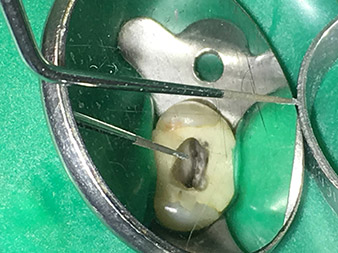

Dr. Nouraie: Yes, in my opinion. The tips allow you to work in a particularly atraumatic and minimally invasive manner. Among other steps, this applies to the exposure of the individual canal accesses, preparation of the cavity in the area of the pulp chamber, rounding off of the canal openings at the transition from the bottom of the chamber to the root canal and preparation of the coronal regions of the root canals.

Dr. Nouraie: I particularly enjoy working with the 1E tip. It is perfectly suited to activating the rinsing fluid in the root canal system. The delicate design of the tip allows you to reach deep sections of the canal too and ensure optimal activation.

Dr. Nouraie: The use of ultrasonic tips allows targeted, atraumatic, minimal removal of substance at the desired site (e.g., when exposing the canal openings, rounding off the cavity floor and exposing broken-off instruments or posts as well as when processing coronal canal sections).

Canal transitions can be smoothed and rounded off with more precision than when using burs. The activation of the rinsing fluid in particular offers enormous advantages that cannot be guaranteed with other instruments. The special instruments from W&H make it possible to perform completely new indications minimally invasively such as revision of broken-off tips and posts.

Pictures: Dr. Shahrad Nouraie Ashtiani, Bremen